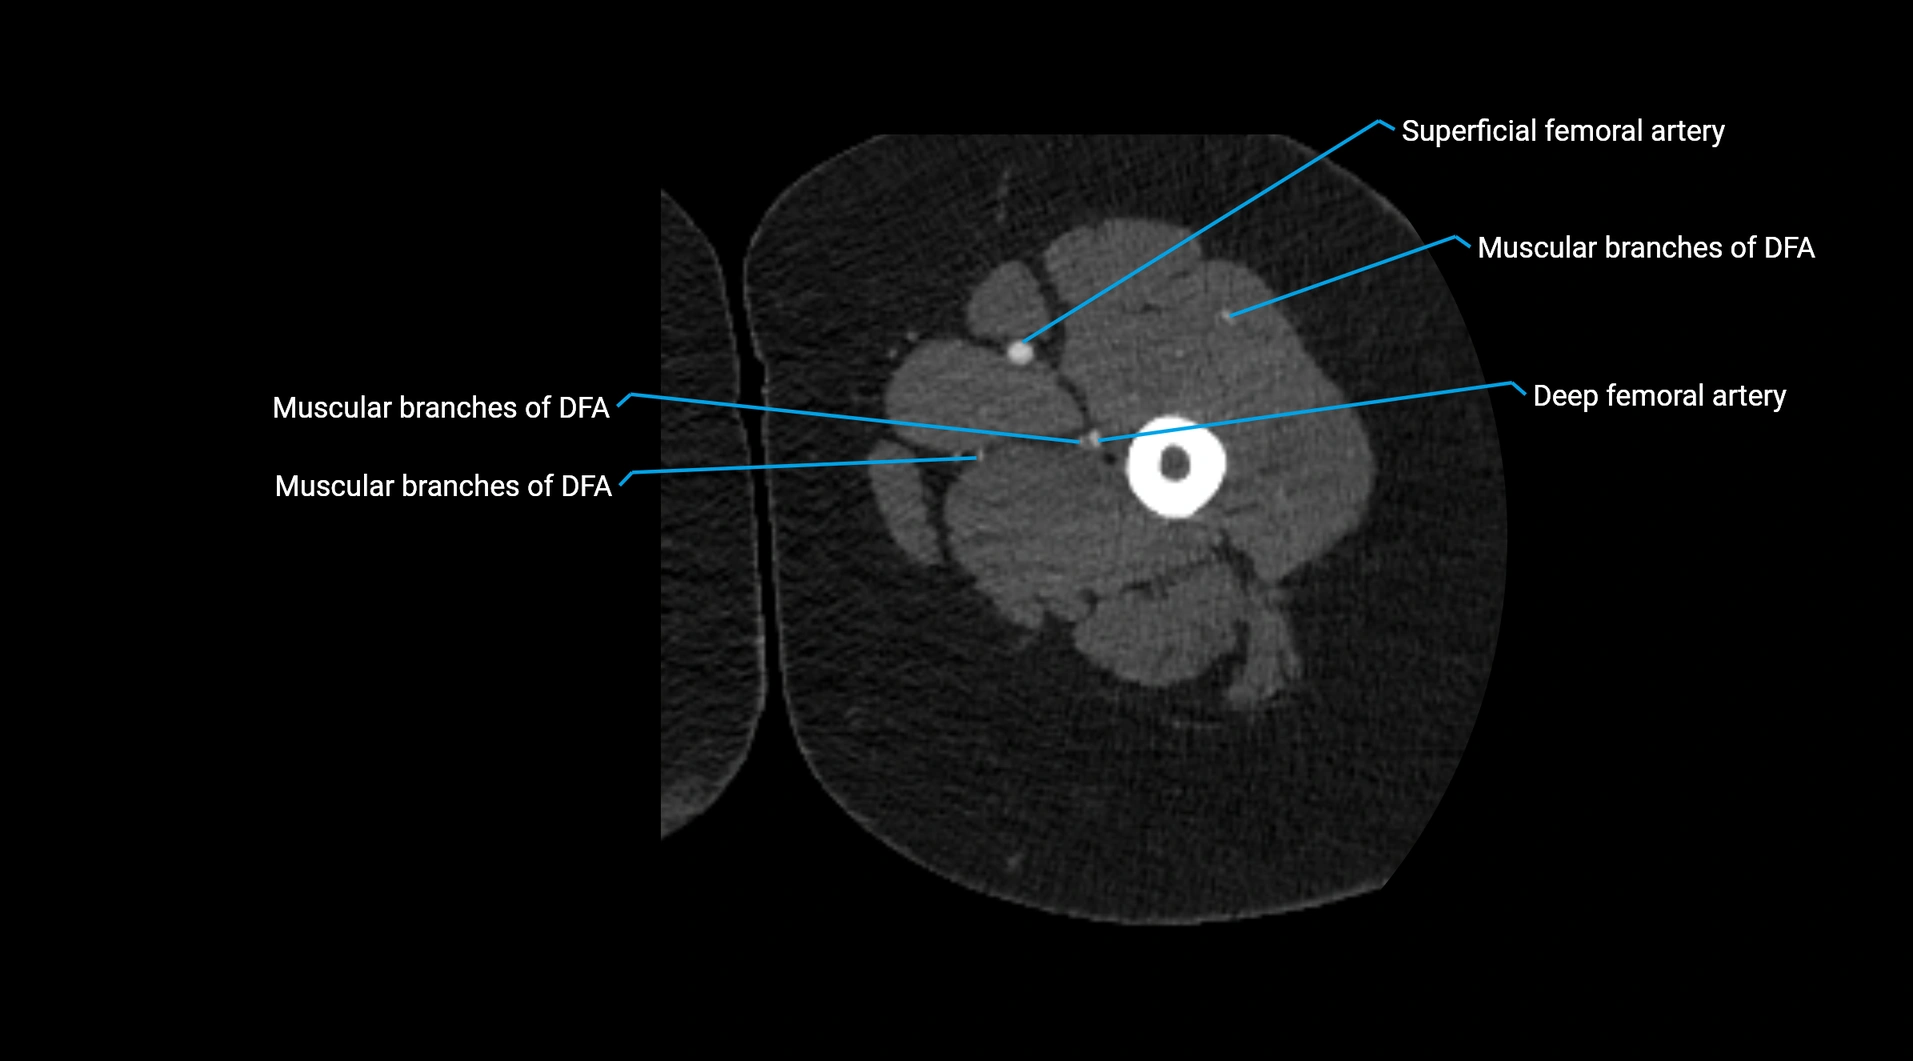

CT Appearance

Contrast-enhanced CT (CTA):

• Gold standard for abdominal aortic imaging

• Provides excellent detail of lumen, wall, aneurysm, thrombus, and branch vessels

• Multiplanar and 3D reconstructions help in aneurysm measurement, stent graft planning, and dissection evaluation

• Detects acute rupture, traumatic injury, or occlusion with high sensitivity

CT images

image